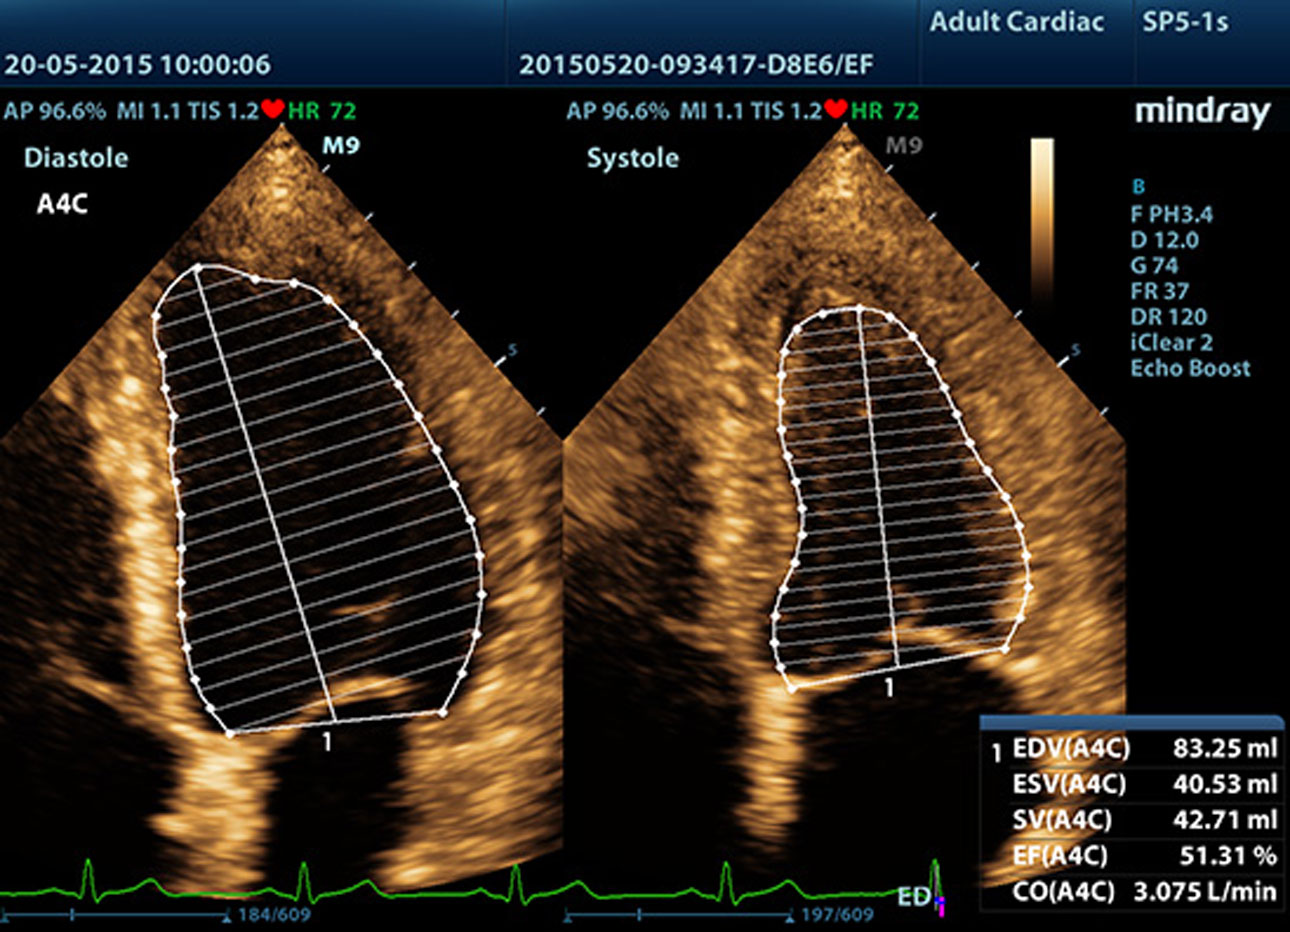

Auto EF (automatyczne wyliczanie frakcji wyrzutowej)

Jeden z inteligentnych sposob├│w analizy fragment├│w nagra┼ä, tzw. ?clip├│wŌĆØ echa 2D, aby mogli Pa┼ästwo automatycznie rozpozna? obrazy faz skurczu/rozkurczu oraz automatycznie wyliczy? parametry i frakcje wyrzutow? EDV/ESV/EF przy u?yciu metody Simpsona.